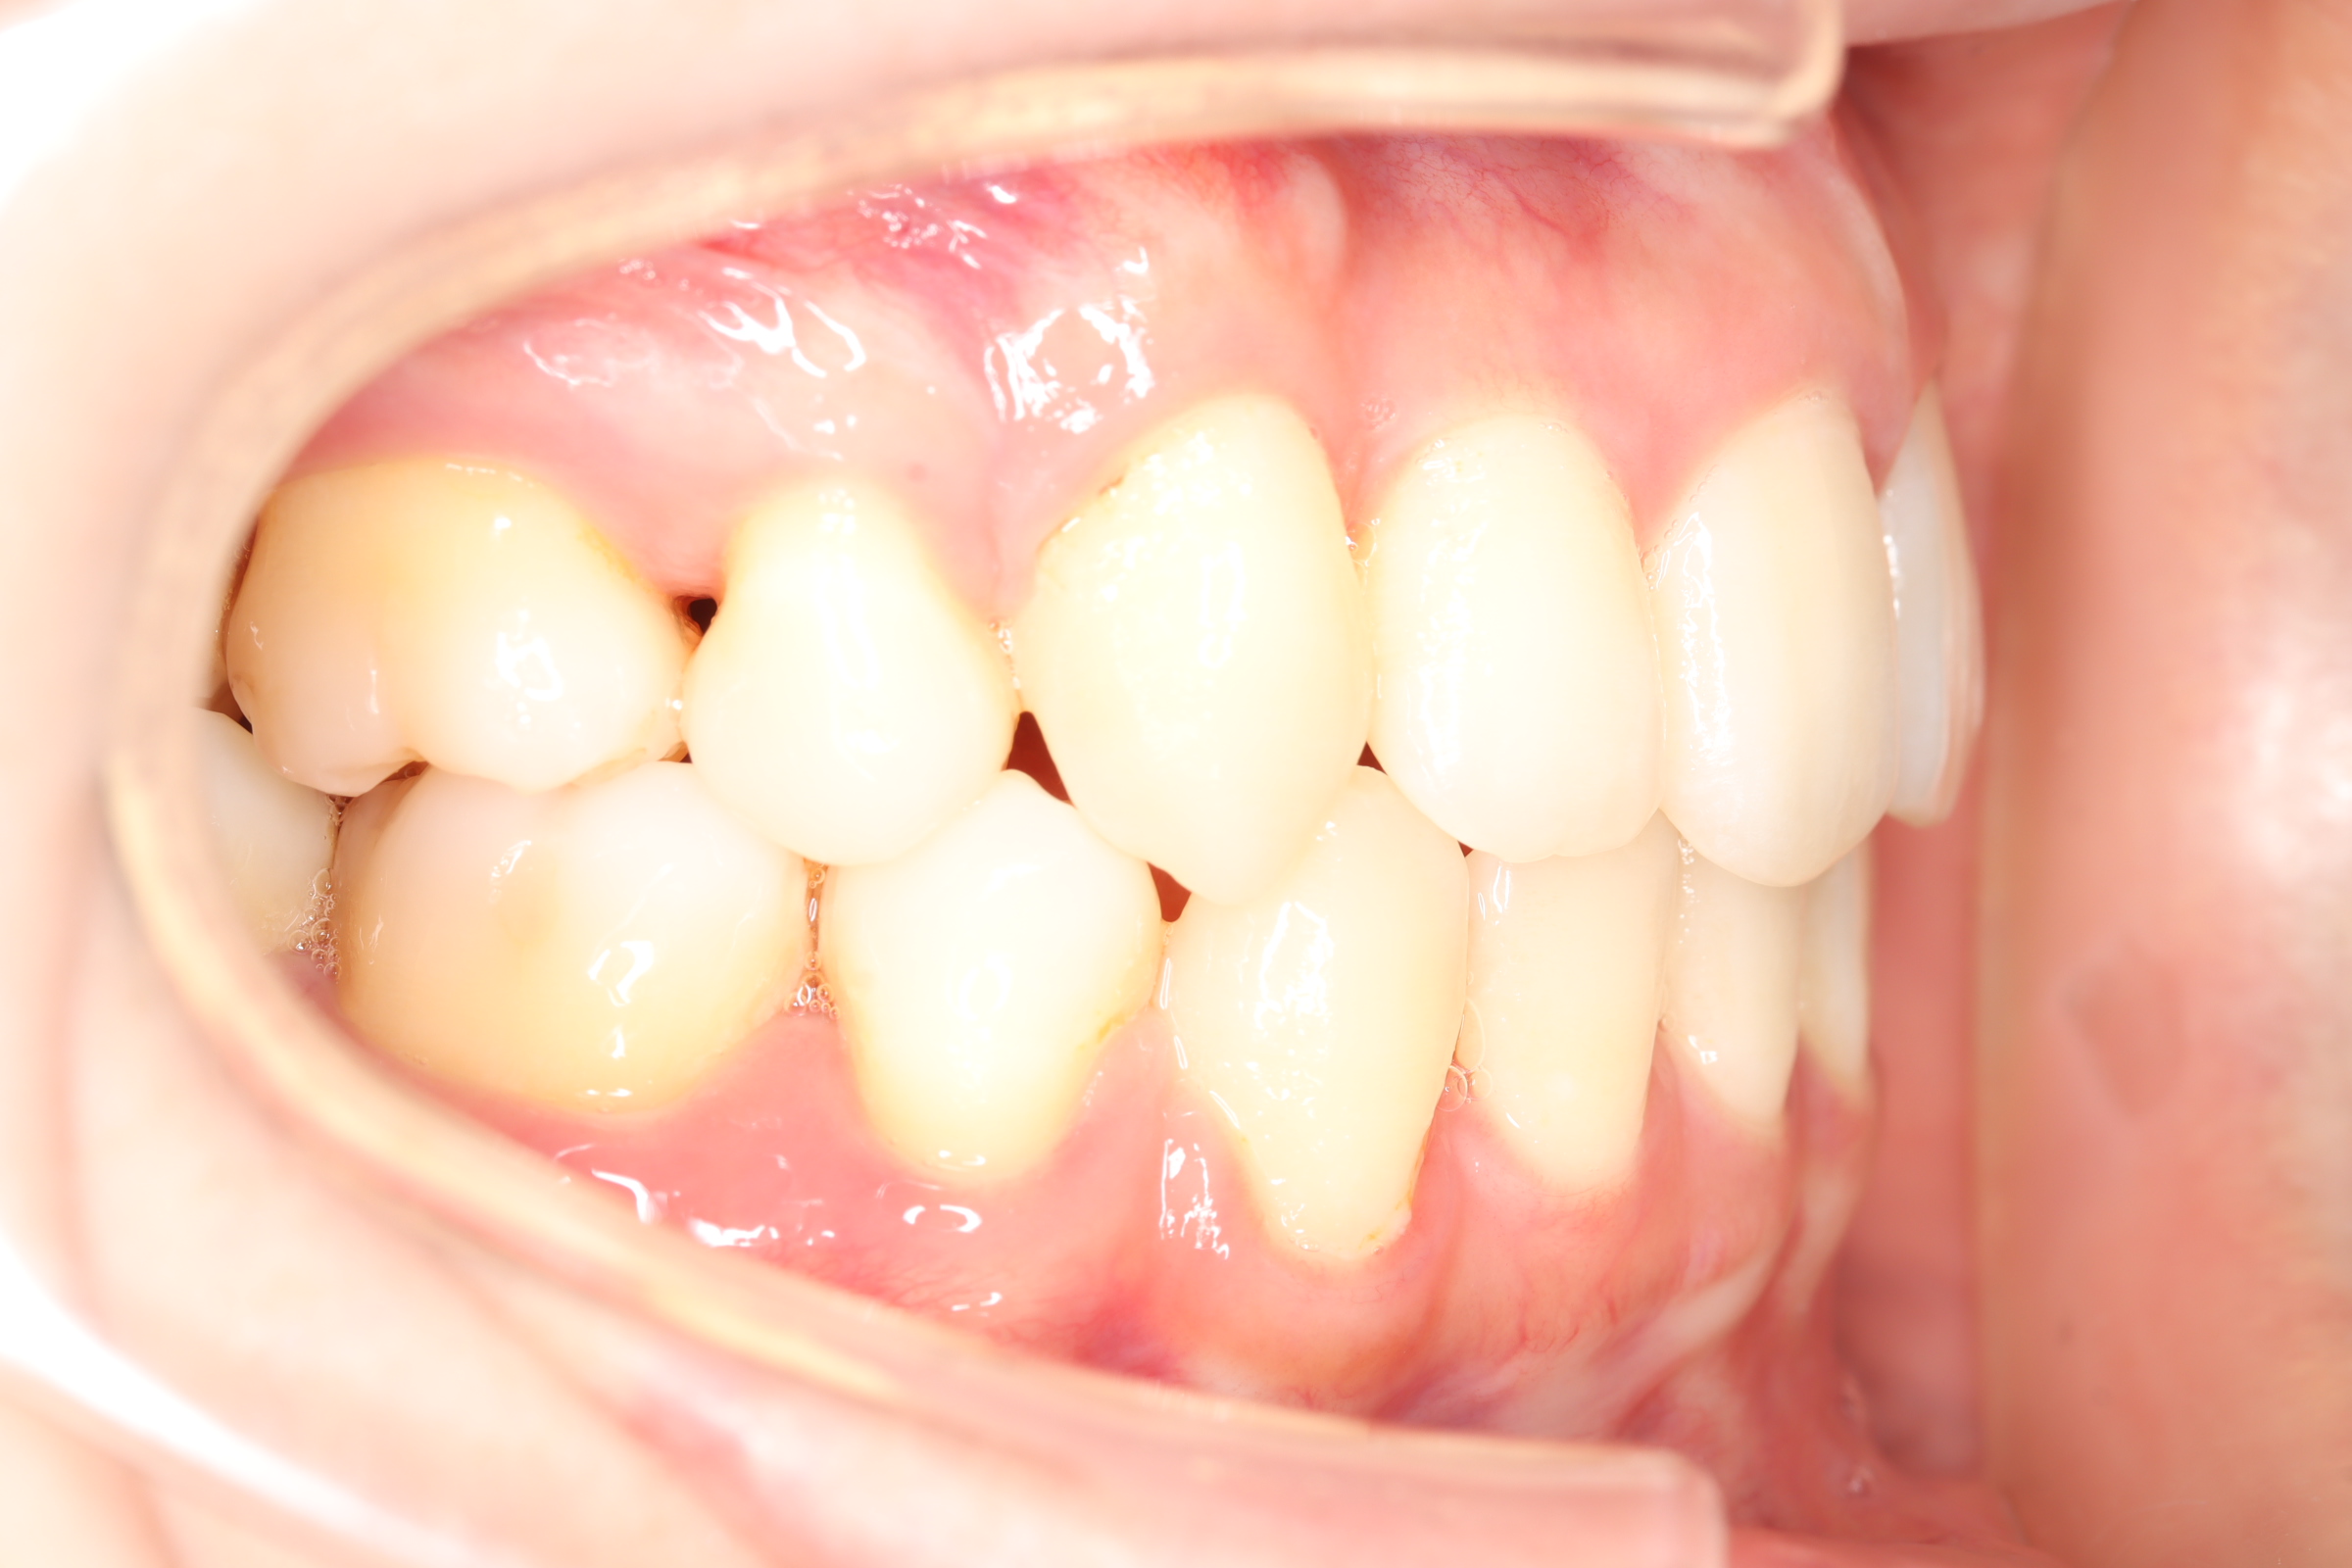

舌側(リンガル)矯正での叢生(ガチャ歯)の治療

口腔内の変化

| 治療前 | SNSなどで「ガチャ歯」と呼ばれている、見た目のがたつきを治したかった患者さんです。 骨格的な問題はありませんでしたが、上下の前歯が唇側傾斜しており、上下顎前突症で口元の突出感がありました。 |

| 治療後 | 前歯から奥歯まで全体的に緊密な咬み合わせになっています。 歯のガタつきが無くなることにより、綺麗な見た目と歯磨きのしやすい口腔内環境になりました。 また突出感のあった口元もすっきりして綺麗なEラインとなり横顔も変化しました。 しっかりとしたかみ合わせを作ることにより、綺麗な歯並びになります。 |